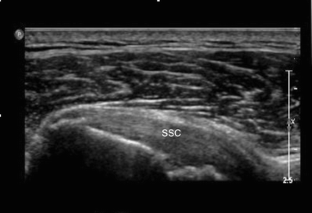

Fig. 4